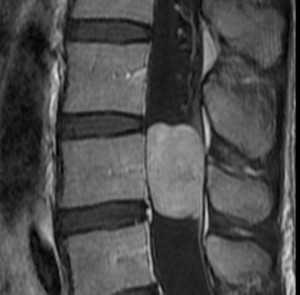

Нейрофиброма. Сагиттальная Т1-зависимая МРТ с контрастированием.